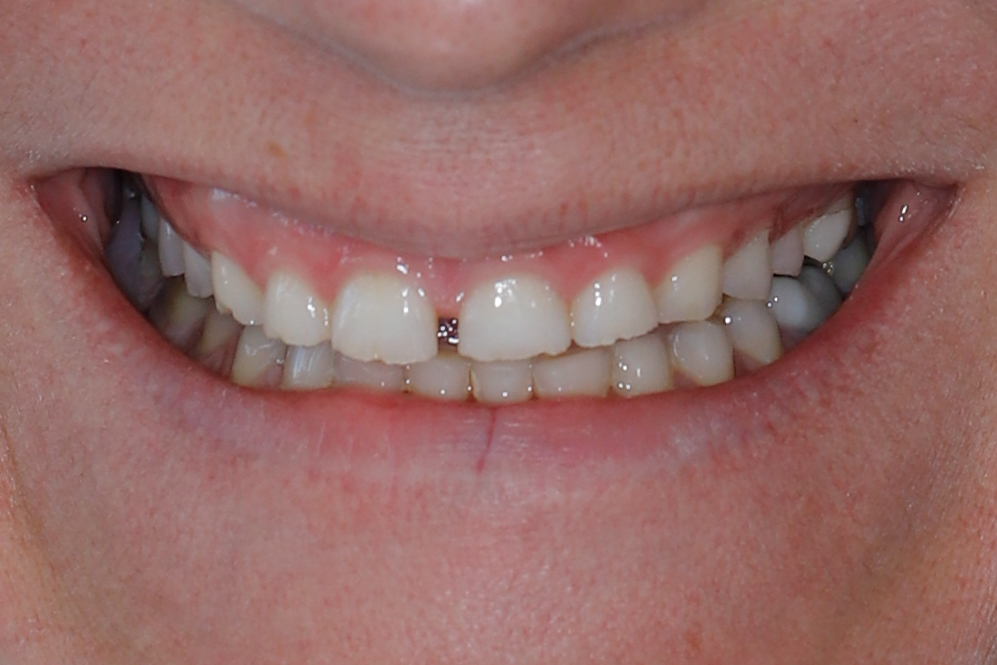

Before

After